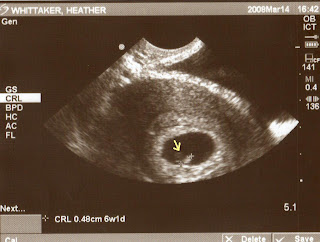

So a couple of days after Tim passed his first actuary test, I passed my pregnancy test. I am now 6 weeks pregnant and other than feeling extremely tired, I'm feeling fairly good. We went to the doctor yesterday and had our first ultrasound. Other than looking like a pulsating lima bean, our baby is healthy. We should be able to meet this little ...boy?... girl? (sorry Dad, it's not a puppy) on November 6th (or somewhere around there). Kudos to Kimmie for figuring out the exact date before we even talked to the doctor!

The arrow is where the baby is at (click it for clarity).